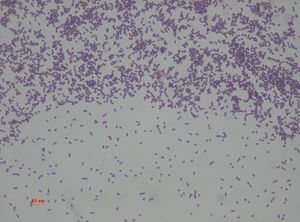

Enterococcus faecalis – formerly classified as part of the group D Streptococcus system – is a Gram-positive, commensal bacterium inhabiting the gastrointestinal tracts of humans and other mammals.[1] Like other species in the genus Enterococcus, E. faecalis is found in healthy humans, but can cause life-threatening infections, especially in the nosocomial (hospital) environment, where the naturally high levels of antibiotic resistance found in E. faecalis contribute to its pathogenicity.[1] E. faecalis has been frequently found in reinfected, root canal-treated teeth in prevalence values ranging from 30% to 90% of the cases.[2] Re-infected root canal-treated teeth are about nine times more likely to harbor E. faecalis than cases of primary infections.[3]